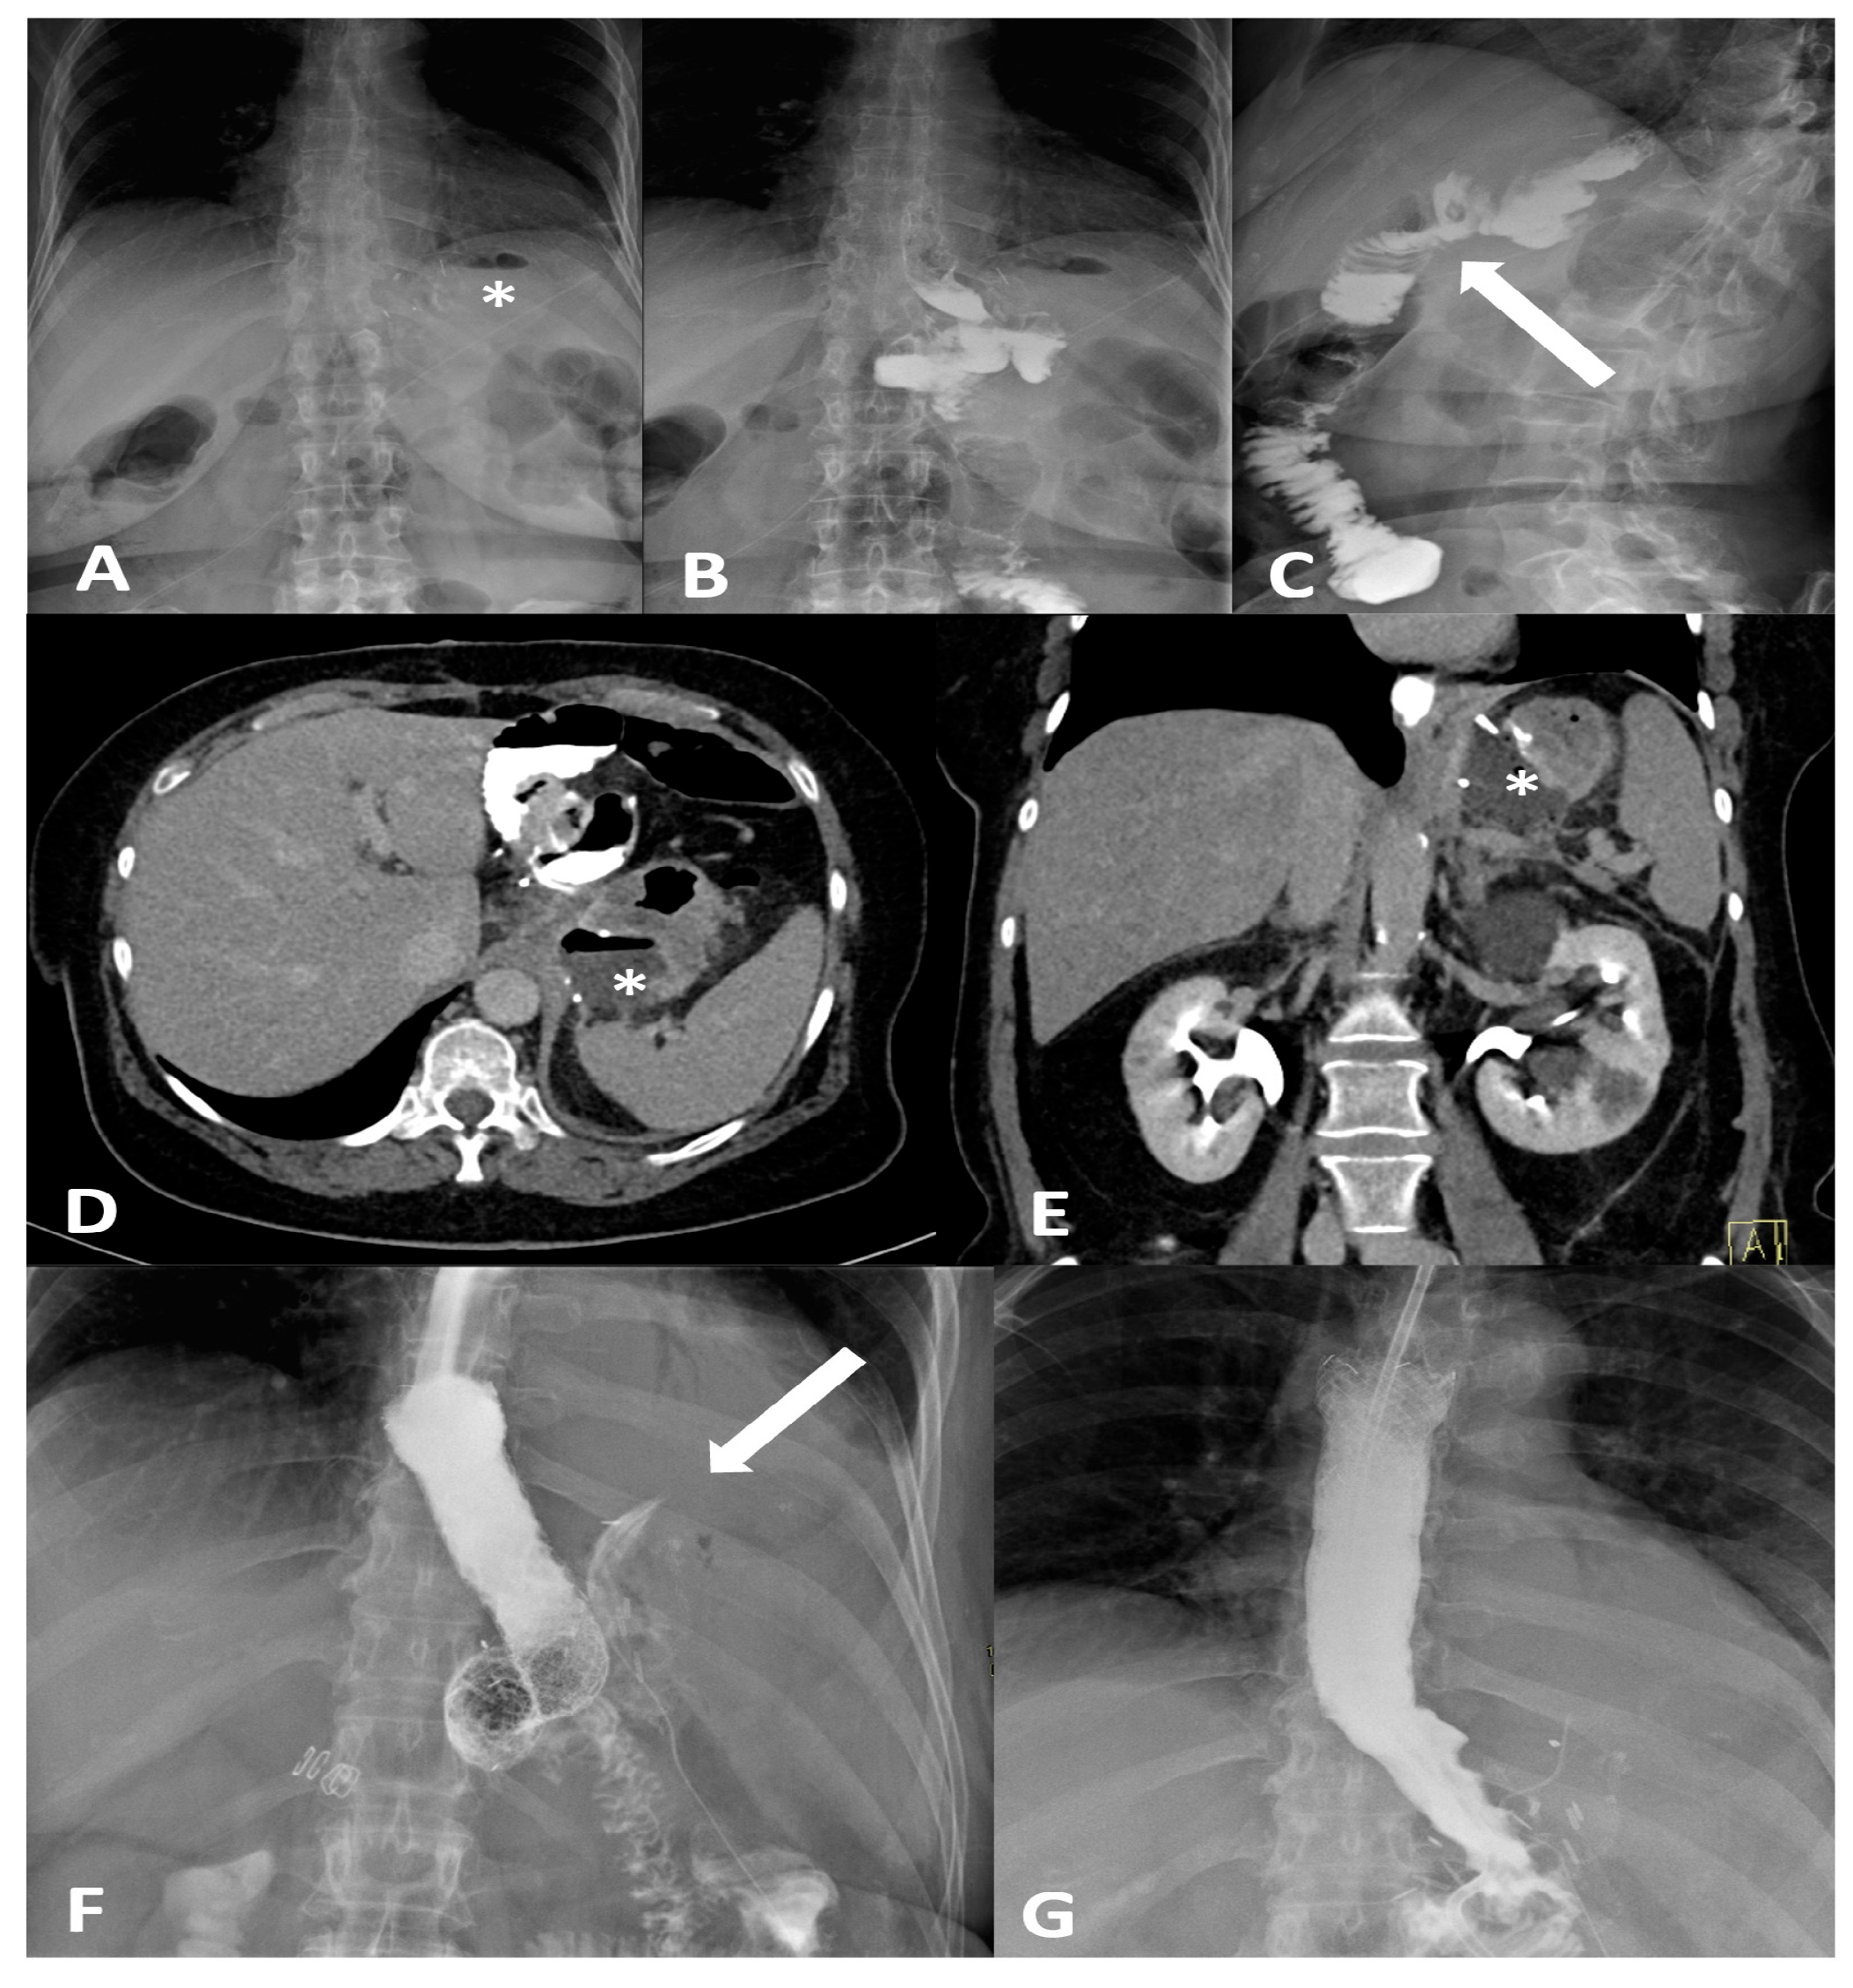

Figure 1.

Frontal (A,B) and oblique (C) X-ray for postoperative bariatric surgery assessment. Surgical clips (asterisk) are visible in the epigastric region and a surgical drain is present in the left hypochondrium. The examination was performed following oral administration of water-soluble contrast agent. The esophagus is patent, with normal caliber and course. The gastrojejunostomy (arrow) shows regular opacification. No extraluminal contrast leakage is observed. Opacified small-bowel loops are seen, without evidence of dilatation. Four days later, following the onset of fever and abdominal pain, the patient was re-evaluated with CT. CT equilibrium-phase axial (D) and coronal (E) scans showing postsurgical changes from gastric bypass with creation of an L–L gastrojejunostomy. Between the medial contour of the gastric remnant and the gastric pouch—inseparable from the left diaphragmatic crus, which appears thickened and slightly heterogeneous—a fluid-containing collection (asterisk) is visible. The adjacent adipose tissue demonstrates a heterogeneous appearance, with several small air bubbles present within it. After the placement of an esophageal stent for protection, the follow-up X-ray with oral contrast (F) shows extraluminal leakage of contrast (arrow) originating from the mid portion of the stent, opacifying a retrogastric collection, as also visible on the CT scans. Ten days later, after placement of a nasojejunal tube, the X-ray with oral contrast (G) no longer shows the previously reported extraluminal leakage. The copyright of this figure belongs to the authors.